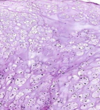

42

Diagnosis Describe Arrow

Liver cirrhosis Loss of the normal lobular architecture which is replaced by regeneration nodules surrounded by fibrous septae. Central veins are absent.The fibrous septae show chronic inflammatory cellular infiltrate Red: regeneration nodules black: fibrous septa